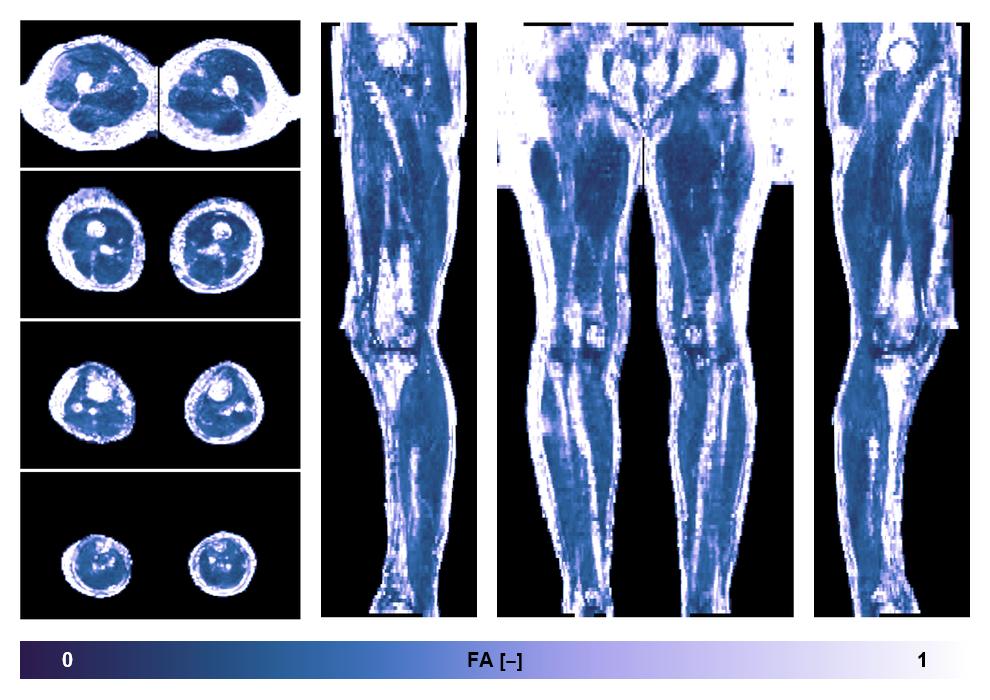

• Fractional anisotropy

IVIM corrected whole leg muscle fractional anisotropy obtained from diffusion tensor imaging.